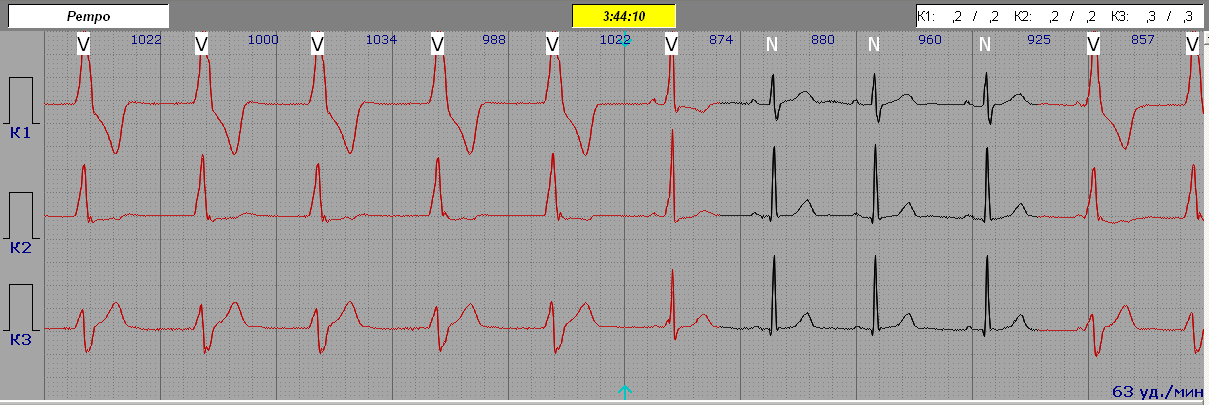

Повільна Шлуночкова Тахікардія (Ідіовентрикулярна Тахікардія) - (ІШТ)

Комплекс QRS спотворений і триває більше 120 мс.

Поступовий початок та поступове згасання (на основі спотворення комплексу QRS).

Інтервали R-R рівні.

Частота серцевих скорочень 100-140